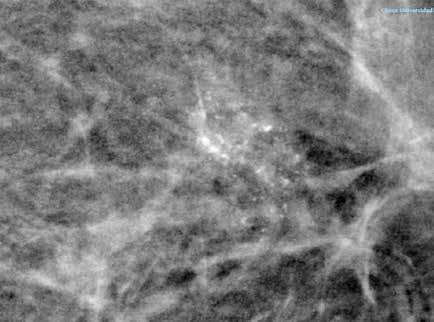

Figura 2.

TC craneal corte transversal. Aumento de la profundidad de los surcos en posible relación a signos de atrofia encefálica acentuada para la edad del paciente sin que se observen claras lesiones focales ni colecciones o signos de sangrado intra o extraaxial. Se observa una tenue hipodensidad del esplenio del cuerpo calloso.